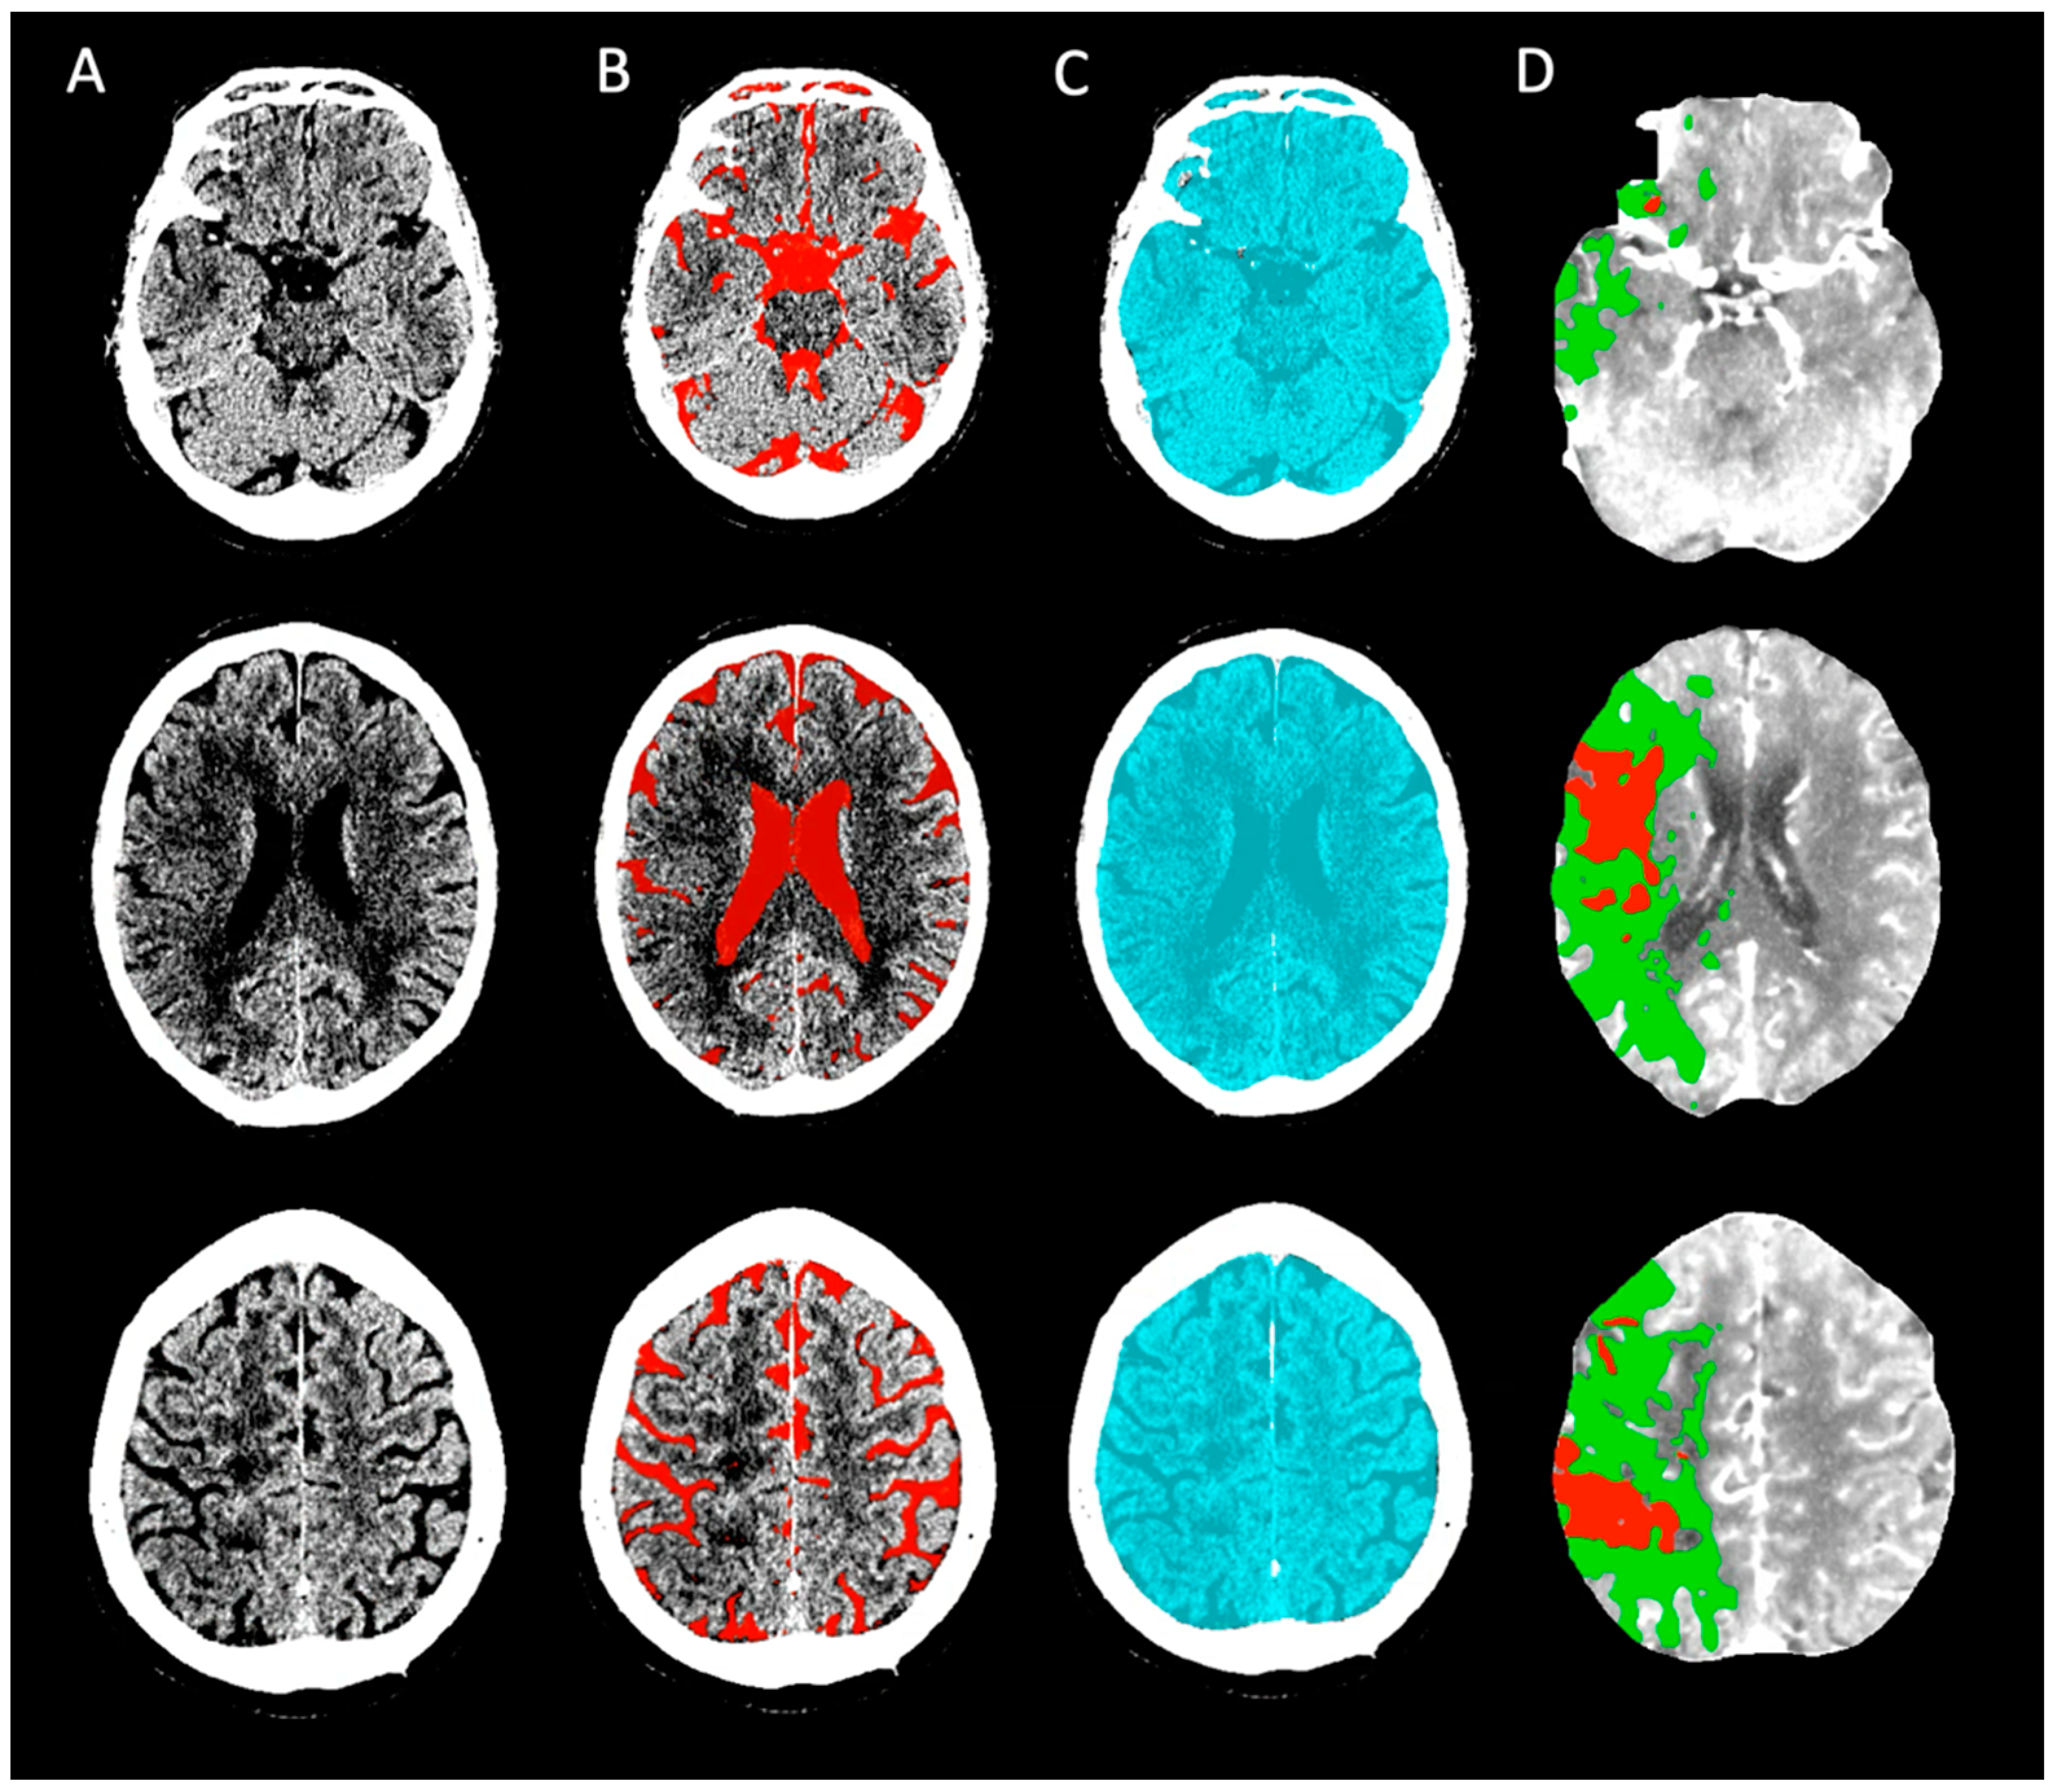

2.2. Baseline Image Acquisition, Post-Processing, and Quality Assessment

2.3. ICV and Cerebrospinal Fluid (CSF) Assessment